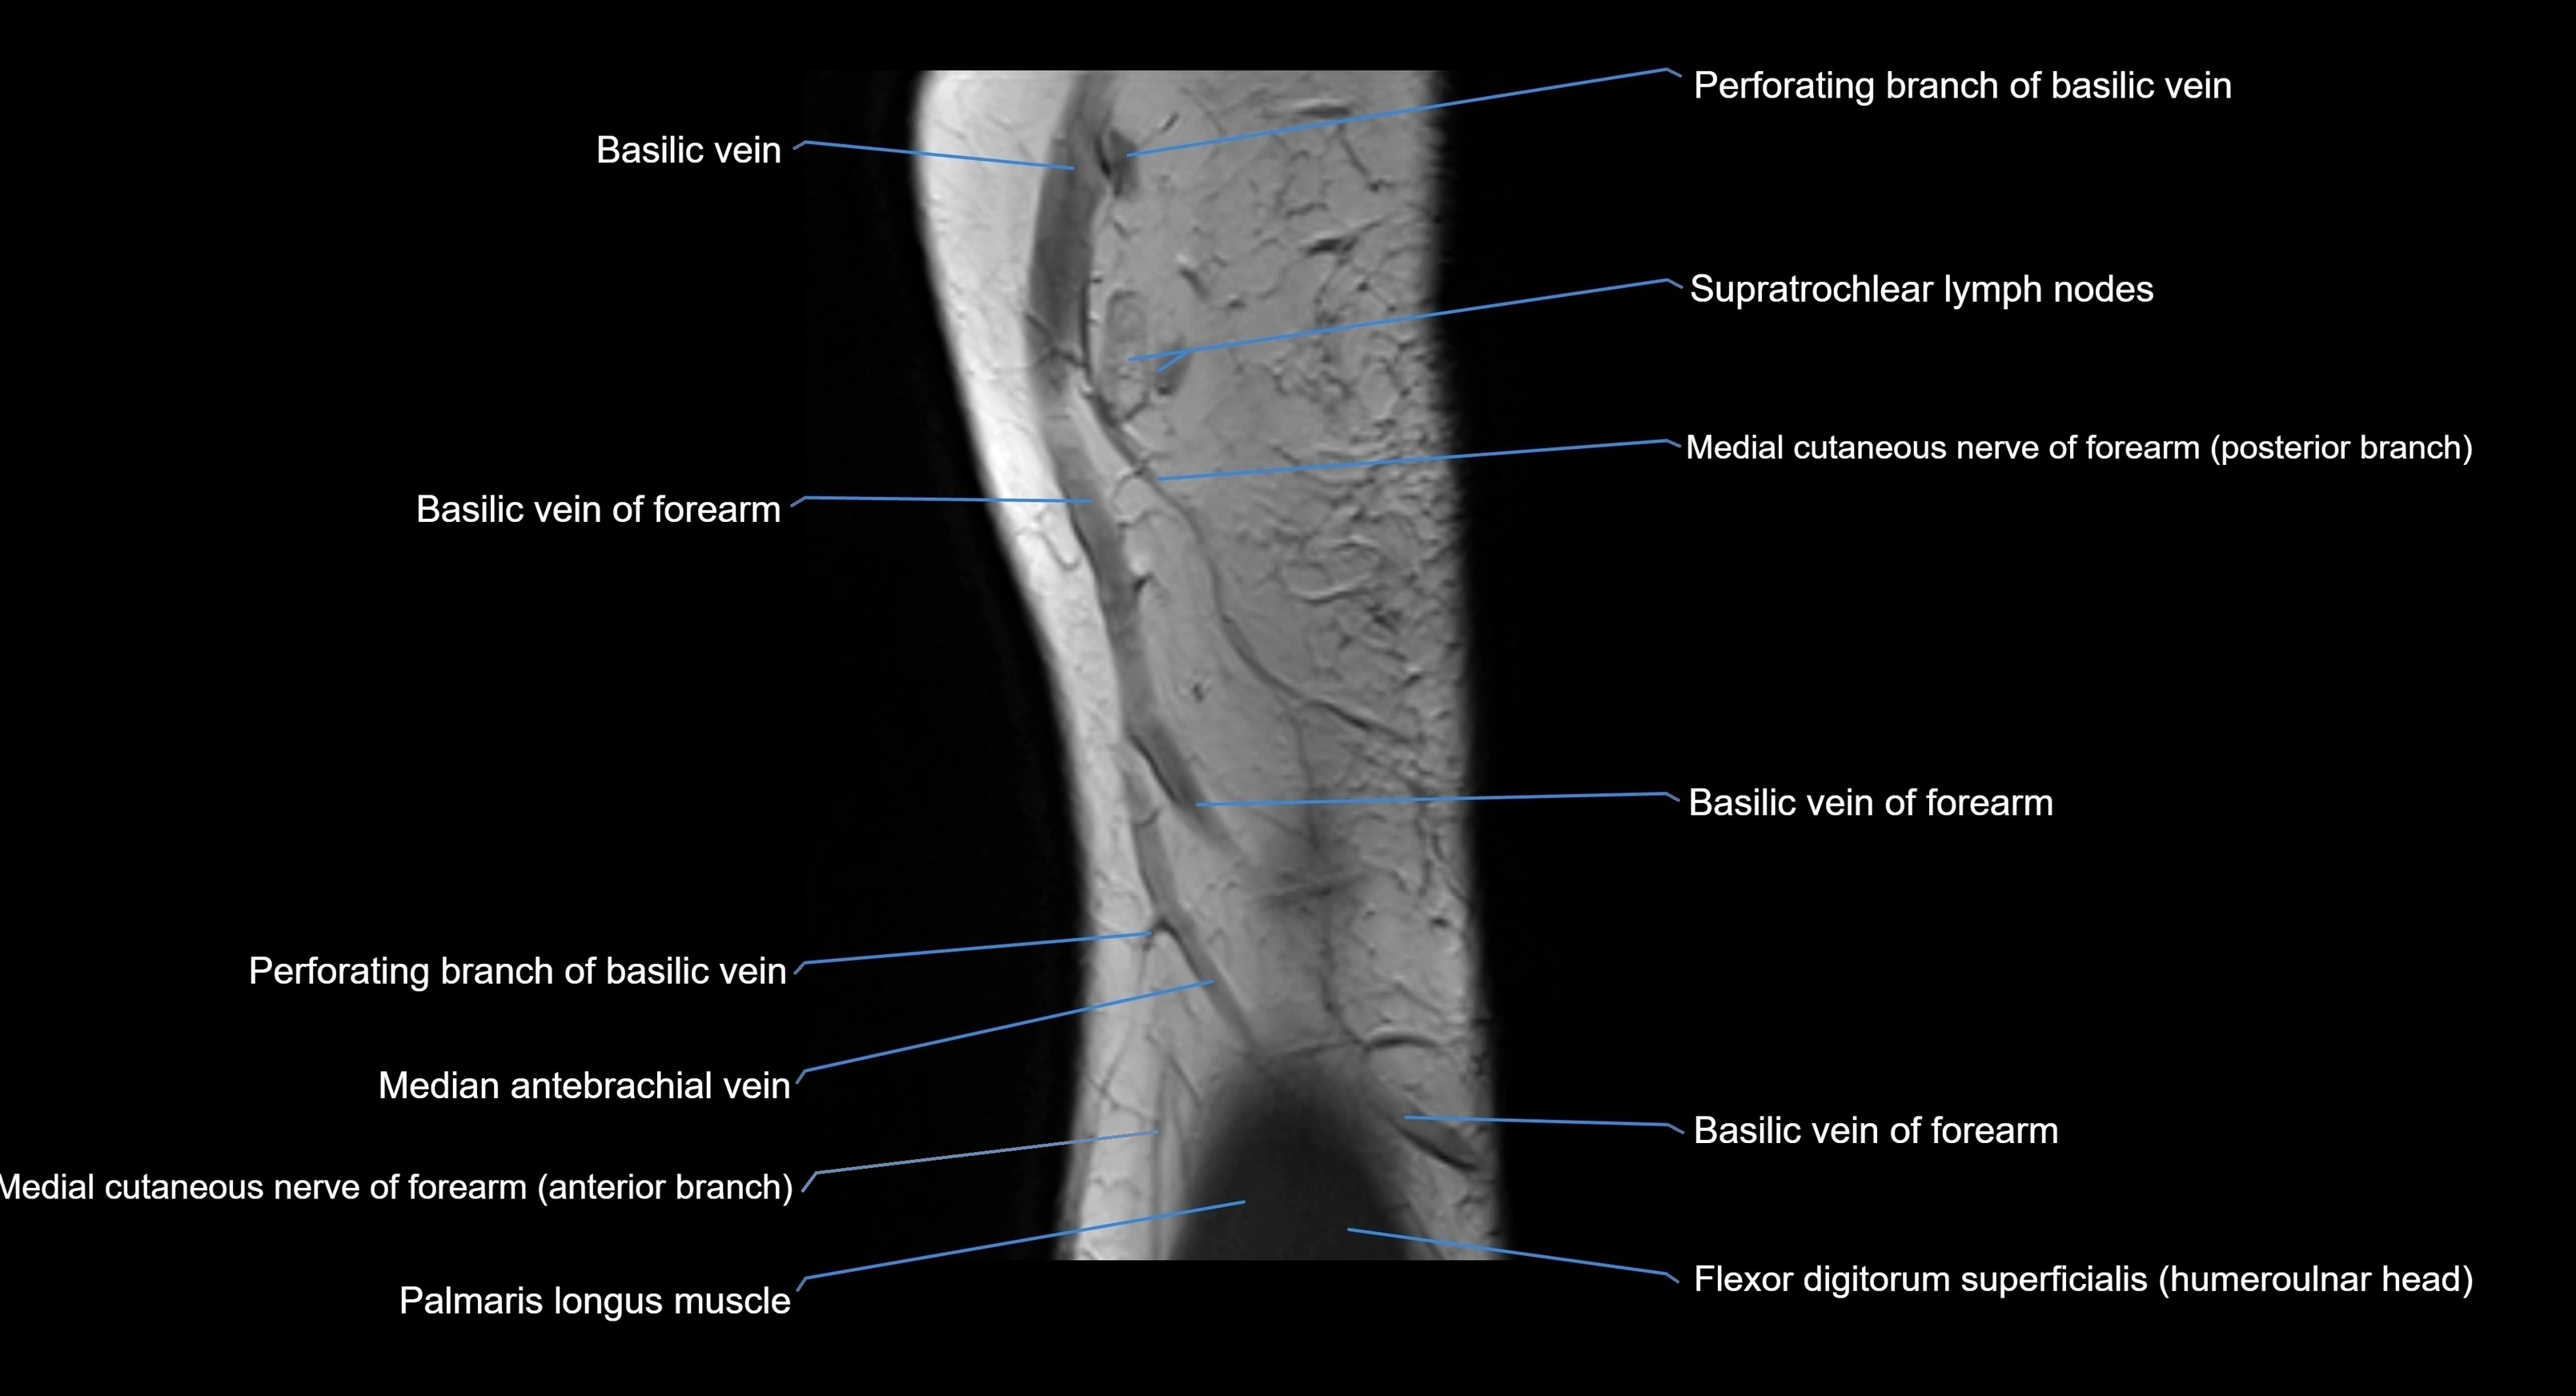

MRI image

image